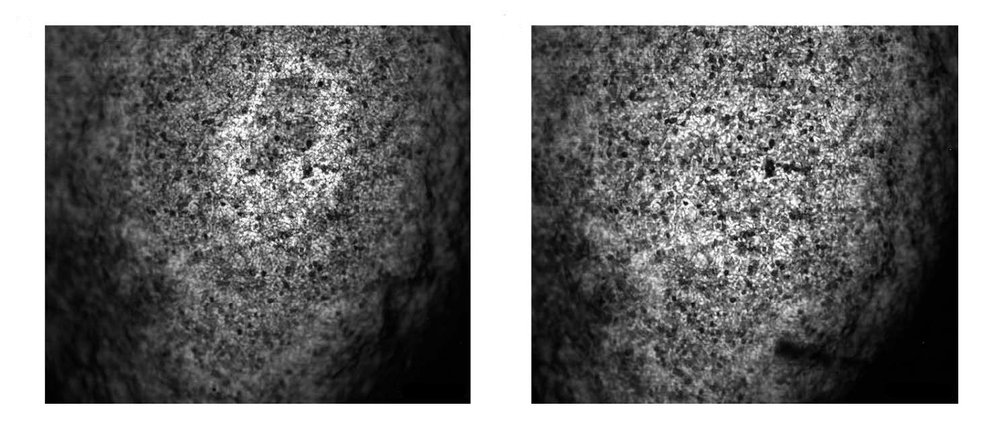

That greater depth of field was demonstrated by the researchers in two ways: imaging fresh organ samples using an ultraviolet laser and imaging in vivo mouse brain vasculature using a blue laser.

In a new paper in the journal Nature Photonics, Wang and his research team show how they developed a new variant of PAM called needle-shaped beam photoacoustic microscopy, or NB-PAM, which that has a depth of field nearly 14 times greater than what was achievable before. This means NB-PAM can create 3-D imagery of samples without refocusing and better image samples with uneven surfaces.

"Some applications, such as studying tissue samples without needing to use a microscope slide, require imaging of uneven surfaces at high spatial resolution," says Rui Cao, lead author and postdoctoral scholar research associate in medical engineering. "Conventional PAM grapples with the trade-off between resolution and depth of field, which has been overcome by our new technology."